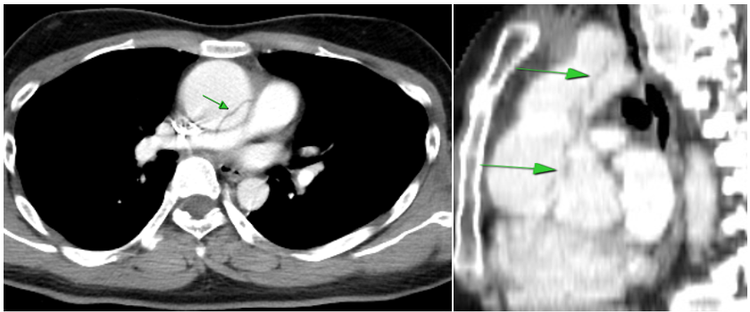

Đây là bệnh lý rất nặng và hiếm gặp, nguy cơ tử vong rất cao. Ngay lập tức anh Q. được chụp phim cắt lớp vi tính lồng ngực xác định chẩn đoán và chuyển sang Viện Tim mạch Quốc gia để phẫu thuật. Quả thực anh Q. đã rất may mắn khi được chẩn đoán và phát hiện, điều trị bệnh kịp thời.

| Hình ảnh động mạch chủ ngực giãn và lóc tách (mũi tên xanh) - Ảnh BSCC |